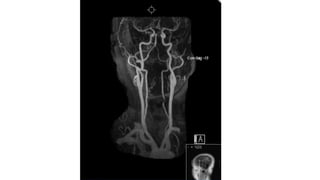

Sub-clavian Steal Syndrome

subclavian artery from the opposite vertebral artery and basilar artery.

• #22 Increased T2-weighted magnetic resonance imaging signal of medial aspect of lower left cerebellar hemisphere and left side of lower vermis. MRI allows better resolution an haence MRI is preferred over CT scan for imaging lesions in the posterior fossa.

• #23 Focal narrowing of the lower cervical segment of the left vertebral artery